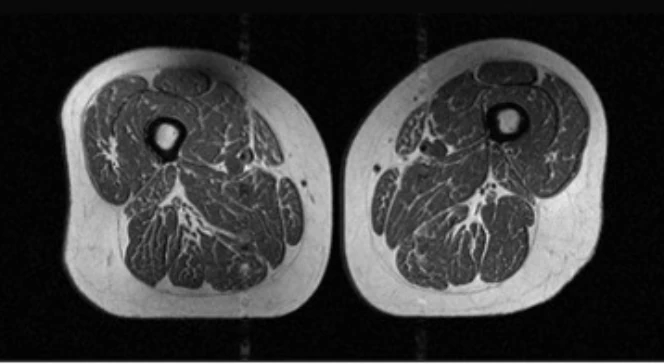

The other image shows the muscles of the woman whose diet is almost 90 percent UPFs.

In the image, you can see the muscles have much more marbling, which means that the fat has accumulated within the thigh muscle and replaced healthy tissue, which ultimately leads to muscle weakening.

The fat buildup makes everyday tasks more strenuous, and walking can become much more difficult as the muscle is weaker.

An MRI scan was done on each participant’s thighs, then researchers analyzed the scans and graded fat infiltration in the thigh muscles.

The study concluded that people who ate and drank higher amounts of UPFs had far greater intramuscular fat, especially in the thighs.